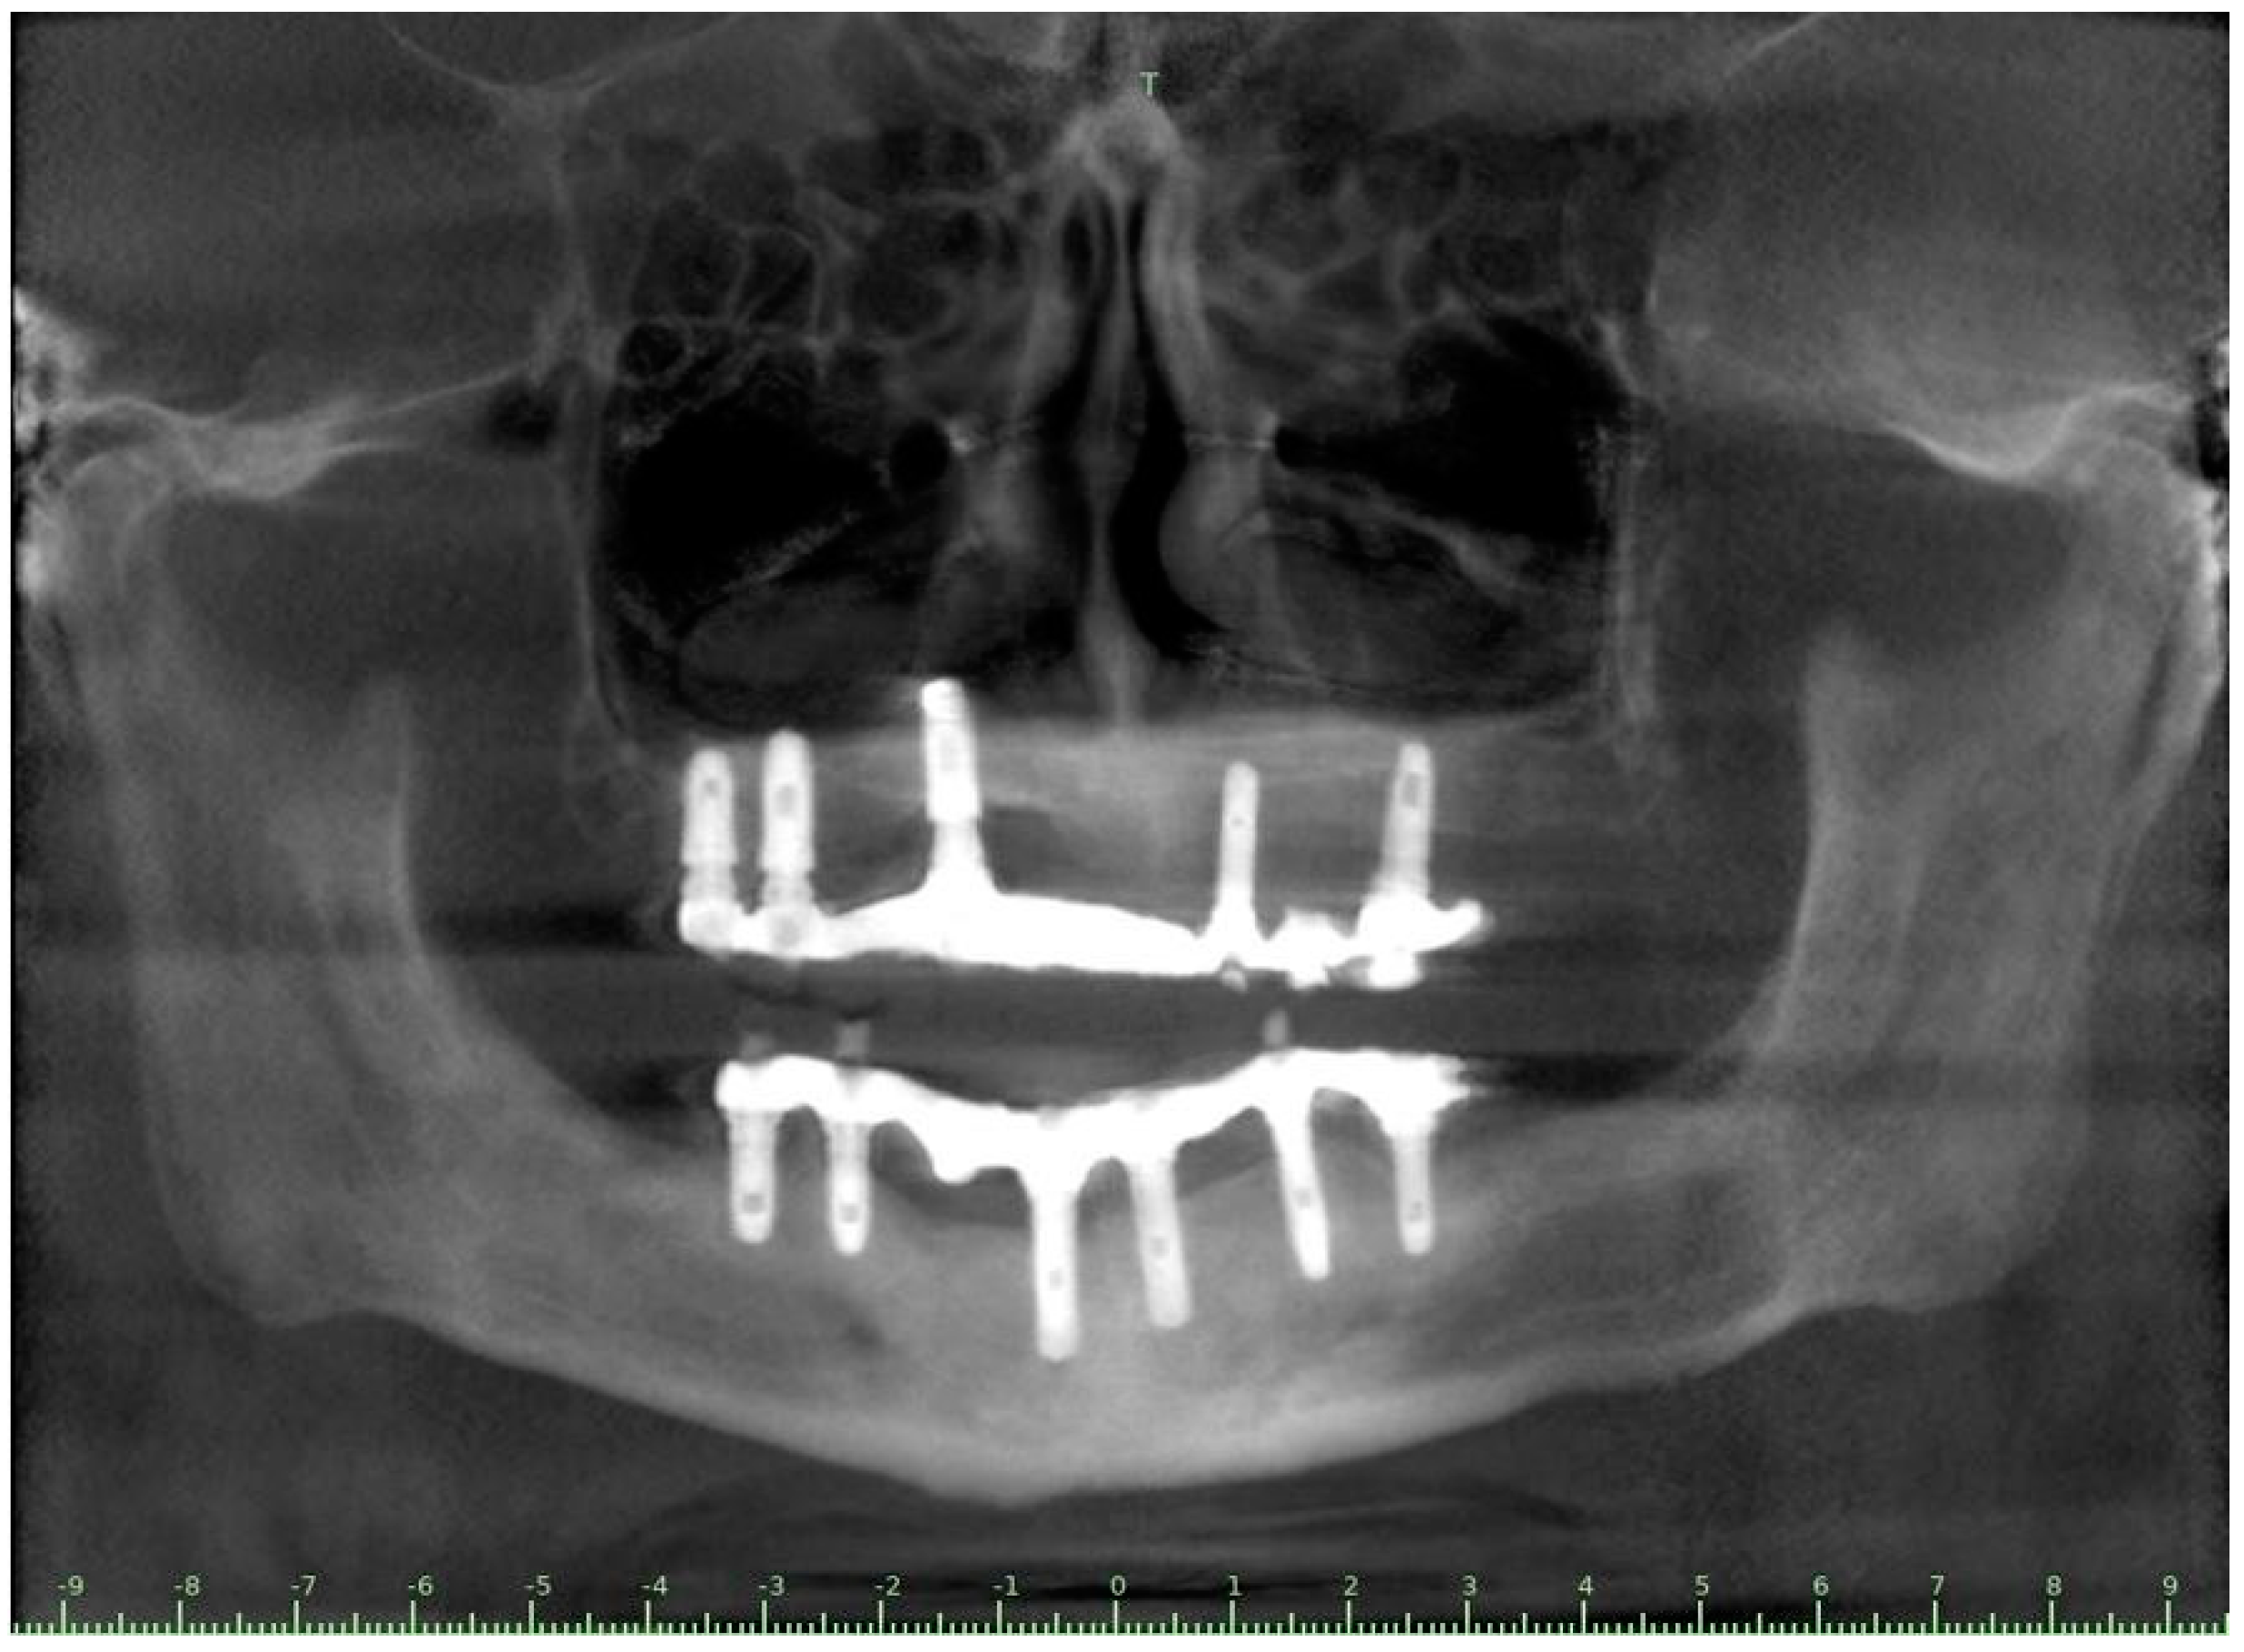

| Flanagan D. et al. [23] | J Oral Implantol | 2015 | clinical and radiographic: full-mouth radiographic series, panoramic and a bimaxillary cone beam computerized scan and mounted study casts | -One patient | Subject of 34 yo male; severely carious teeth and associated chronic abscesses (kidney transplant delayed) Comorbidities: IgA nephropathy, tabagism, hypertension and secondary hyperparathyroidism. Hemodialysis three times weekly. Ph. Therapy: Nephrocaps vitamin (B) supplement, amlodepine, besylate, cinacalcet, metoprolol, paroxetine. Bilateral compound ulnar and radial fractures, 2 blood transfusions. | Successfully treated with dental implant-supported fixed prostheses: fixed bimaxillary porcelain fused to metal implant-supported complete dentures |

| Flanagan D. et al. [23] | J Oral Implantol | 2015 | -Implant treatment for patients with IgA nephropathy (secondary hyperparathyroidism and osteodystrophy) may be successful. -Appropriate calcium therapy is important serum calcium to prevent inappropriate bone remodeling | 2 years | Long-term dialysis patient with end-stage renal disease (ESRD)also referred to as chronic kidney disease (CKD) due to IgA nephropathy complicated by severe secondary hyperparathyroidism and renal osteodystrophy | |